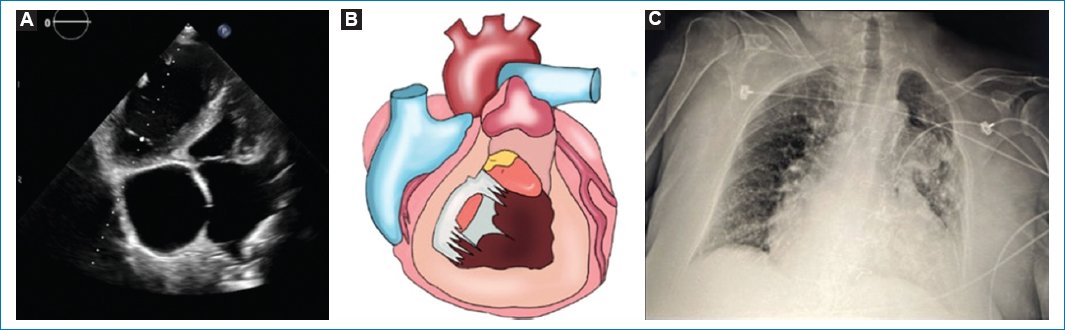

In the examination, there was a remarkably generalized pitting edema of 1 year of evolution Godett 4+, with hot and painful erythema in the lower hemiabdomen and lower limbs of 2 weeks of evolution, and peribuccal cyanosis. The pulse rate was 65 beats/min; blood pressure of 137/75; respiratory rate of 16/min, and oxygen saturation of 75%. Complementary diagnostic studies were performed to complete the clinical assesment (Fig. 1). The electrocardiogram showed a non-sinus rhythm (Fig. 2), with a right bundle branch block and atrial tachycardia with a 3rd grade atrioventricular (AV) block, with non-specific intraventricular conduction alterations and secondary ventricular alterations. The echocardiogram showed chronic changes with cardiac remodeling characterized by a remarkable dilatation of both atria and right ventricle, and a hypertrophic interventricular septum.

Figure 1. A: four-chamber view on transthoracic echocardiography: showing dilation of both atria, atrial septal defect, hypertrophic interventricular septum, and a small left ventricle chamber due to right ventricle dilation. B: illustration of cardiac remodeling due to congenital heart disease. C: radiography with data of pulmonary congestion and cardiomegaly.